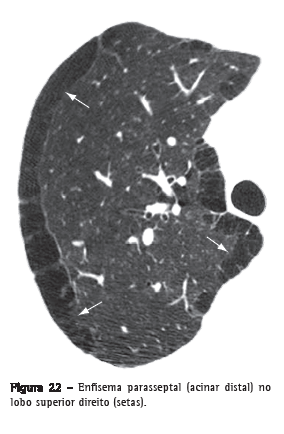

Enfisema parasseptal (acinar distal)Enfisema que envolve predominantemente os alvéolos distais, seus ductos e sacos alveolares. Caracteristicamente, é delimitado por qualquer superfície pleural ou septos interlobulares. Na TC, caracteriza-se por áreas de baixa atenuação nas regiões subpleurais e peribroncovasculares, separadas por septo interlobular intacto (Figura 22).(37,38) Algumas vezes associa-se a bolhas.